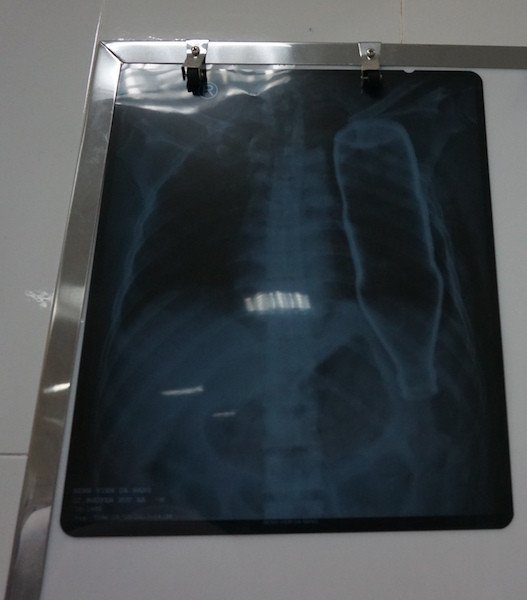

Kết quả chụp X quang cho thấy một vỏ chai thuỷ tinh nằm nguyên vẹn trong lồng ngực của bệnh nhân B. Sau khi hội chẩn, các bác sĩ đã nhanh chóng tiến phẫu thuật lấy chai thủy tinh ra ngoài.

Hình ảnh chai thủy tinh sau khi chui tọt vào lồng ngực bệnh nhân vẫn còn nguyên vẹn.